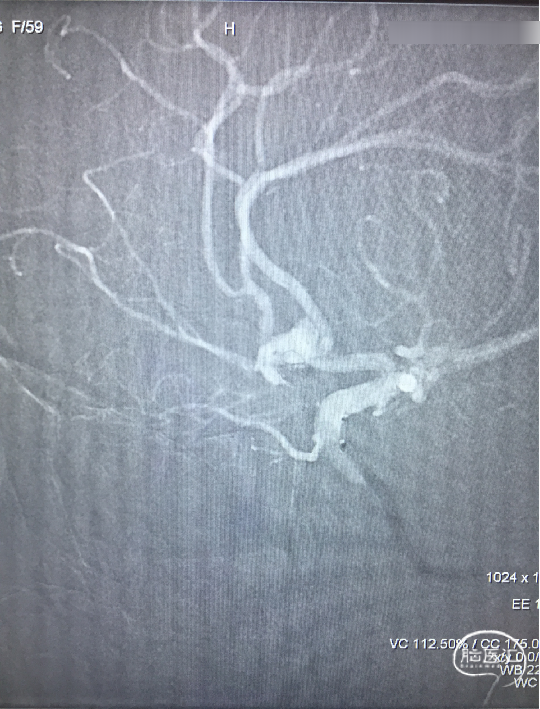

栓塞后即刻影像

工作角度造影显示动脉瘤栓塞致密,LACA A1、ACoA、双A2显影良好,左A2似有血栓(左图)。直头SL-10退至LACA A1末端,推注替罗非班1ml(右图)。

用药后再造影

再造影,发现RACA A2显影差,局部推注替洛非班无效,考虑前交通动脉血流受限,决定支架内球囊扩张。